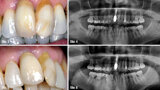

Triumfy a tragédie v implantologii